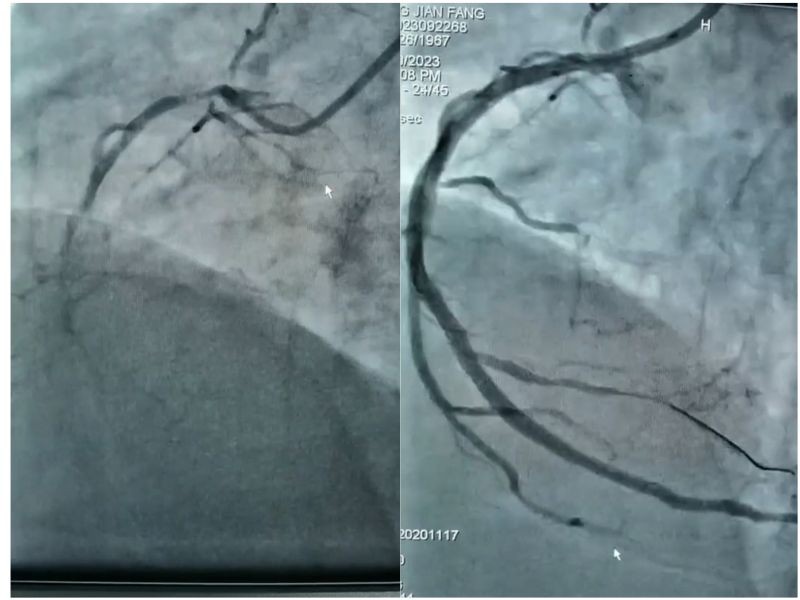

来自广西某县的蒋女士因心脏不适,在当地住院期间突发心衰,县医院紧急联系转院治疗。当救护车把蒋女士送到南溪山医院时,她的右冠状动脉急性闭塞,同时伴有急性左心衰发作,情况危急!心内科一病区的邓英松和张红雨两位副主任医师立刻进行急诊手术开通闭塞右冠,把她从鬼门关抢救回来。

检查发现,蒋女士出现急性心衰主要是因为冠脉病变。人的心脏有三大血管,分别是右冠状动脉、左冠状动脉(左主干)分流的左前降支和左回旋支,其中左冠状动脉供应着80%以上的心肌血量。蒋女士右冠状动脉急性闭塞的同时,前降支近段慢性闭塞,回旋支远段次全闭塞,严重影响供血,相当于一棵大树的主要枝干无法正常输送营养,树会枯萎。有数据显示,冠心病患者中超过70%的病例是由左主干狭窄造成的死亡。

目前治疗的主要手段有外科的动脉搭桥手术或微创介入的支架植入术,患者综合考虑选择了后者。作为蒋女士主诊医师的邓英松,已经有丰富的冠状动脉介入术(PCI)治疗经验,他知道蒋女士冠脉病变十分严重,手术难度系数和风险都极高。为确保治疗的安全性和精准行,邓英松采用先进的“血管内超声检查”技术,为患者精准定位支架位置,和介入团队详细制定了手术方案,经过多学科综合配合,一次性解决了左主干分叉病变+前降支慢性闭塞病变+回旋支次全闭塞病变,经造影检查右冠通畅,左冠形成良好循环供血,完全血运重建。目前患者恢复良好,准备出院。